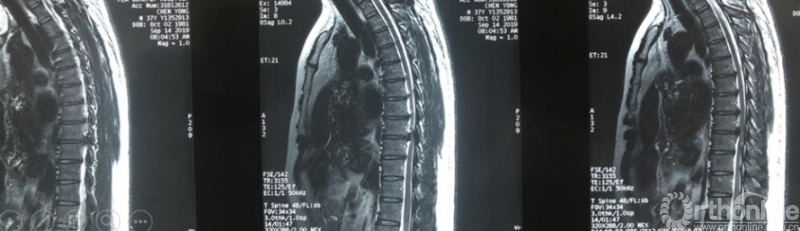

影像学资料

术中资料

同一侧一次两个节段减压,择期对侧进行两个节段减压,两侧腹侧减压范围可达到硬膜囊360度环形减压效果。术后复查硬膜囊环形减压效果。关节突关节破坏较多,需长期佩戴支具固定,保证术后脊柱稳定性。

术后复查资料